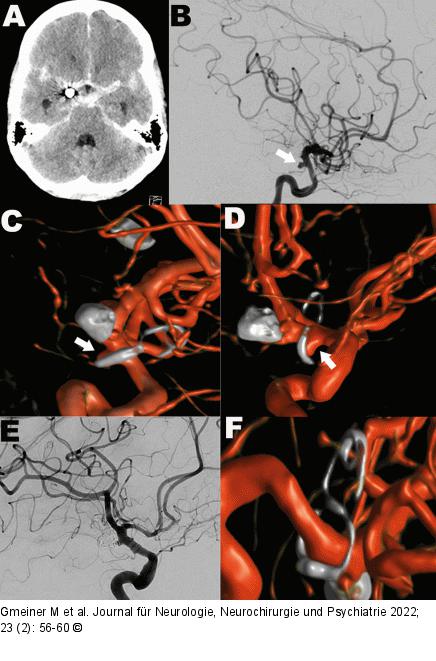

Abbildung 3: Aneurysma Restaneurysma in der intraoperativen 3D-Rotationsangiographie: A: Präoperatives Schädel-CT bei Subarachnoidalblutung. B: Die präoperative Angiographie zeigt ein rupturiertes Ramus communicans posterior-Aneurysma (Pfeil; Z. n. Coiling eines A. choroidea anterior-Aneurysmas). C: Die erste intraoperative Angiographie zeigt ein Restaneurysma (Pfeil). D: Nach Clip-Repositionierung besteht auch in der zweiten intraoperativen Angiographie ein Restaneurysma (Pfeil). E, F: Nach Clip-Repositionierung ist das Aneurysma regelrecht aus der Zirkulation ausgeschaltet. |

Restaneurysma in der intraoperativen 3D-Rotationsangiographie: A: Präoperatives Schädel-CT bei Subarachnoidalblutung. B: Die präoperative Angiographie zeigt ein rupturiertes Ramus communicans posterior-Aneurysma (Pfeil; Z. n. Coiling eines A. choroidea anterior-Aneurysmas). C: Die erste intraoperative Angiographie zeigt ein Restaneurysma (Pfeil). D: Nach Clip-Repositionierung besteht auch in der zweiten intraoperativen Angiographie ein Restaneurysma (Pfeil). E, F: Nach Clip-Repositionierung ist das Aneurysma regelrecht aus der Zirkulation ausgeschaltet. |